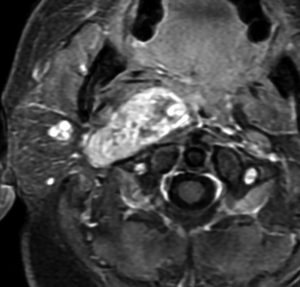

症例:頸静脈孔より下の深頸部のもの:副咽頭間隙腫瘍

左頸静脈孔の下の迷走神経節から発生したものです。ごく軽い飲み込み辛さだけが症状でした。

内頚動脈を強く圧排して,外形動脈からはかなり豊富な血流が流入しています。頭頸部外科で顎骨を割るような手術を計画されていました。

でも,右側の画像で見るような角度から,小さな頸部の皮膚切開だけで,胸鎖乳突筋だけを乳様突起から外して翻展して摘出できました。内部からほじくるように摘出すれば症状悪化はないのですが,周囲軟部組織から切断して剥離しようとすると厳しい嚥下障害と嗄声になります。

手術で全摘出しましたが嚥下障害などはでませんでした。普通のおとなしい神経鞘腫ですから再発はありません。